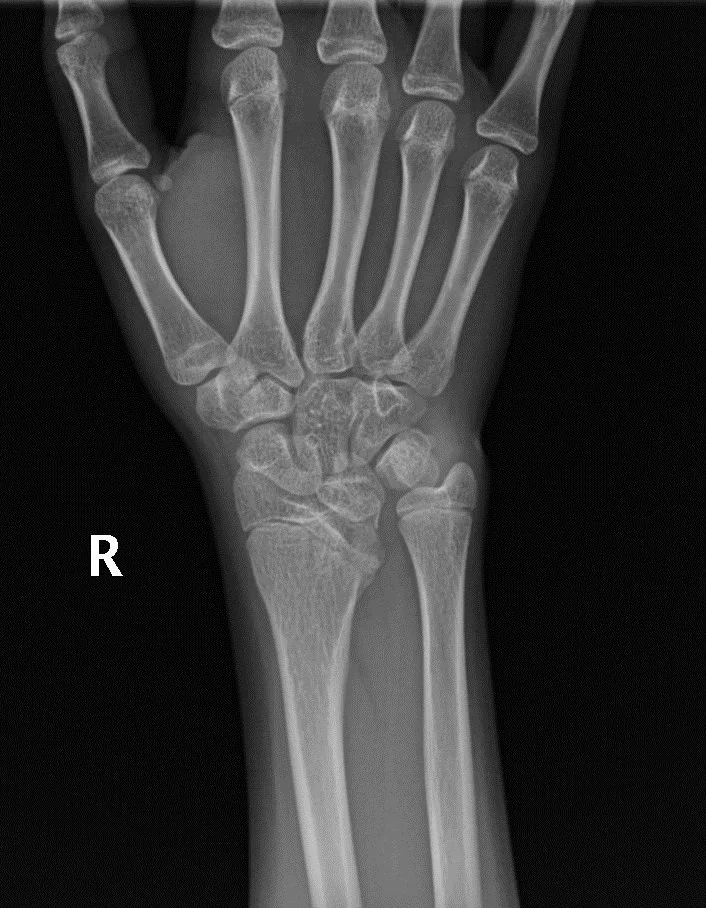

Ulnar Variance

• Refers to distance between the distal radius and ulna (independent of styloid process)

• Neutral - ulna and radius articulatory surfaces are at the same level

• Positive - Ulna projects more distally than radius (>2.5 mm beyond radius margin at DRUJ)

• Associated with ulnar impaction syndrome

• Negative - Ulna projects more proximally than radius (<2.5 mm beyond radius margin at DRUJ)

• Associated with Kienbock & Ulnar impingement syndrome

• Case courtesy of Leonardo Lustosa, Radiopaedia.org, rID: 180779 (ulnar variance)